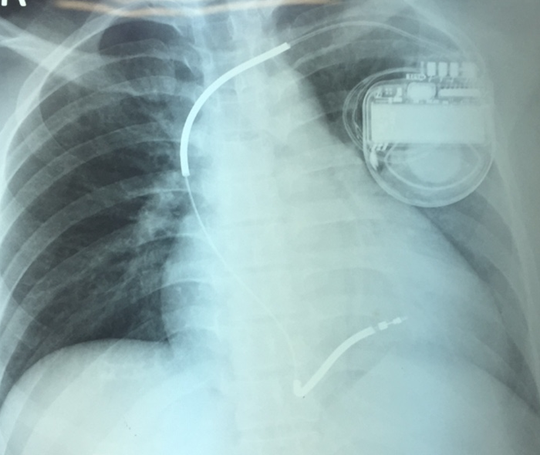

Chiếc máy được cấy vào ngực người bệnh.

BS - CKII Nguyễn Tri Thức, Phó Giám đốc Trung tâm tim mạch Bệnh viện Chợ Rẫy, cho hay khi người bệnh gặp bất trắc, chiếc máy này tự kích hoạt để đưa nhịp tim họ trở lại bình thường. Máy được cấy vào người có thể sử dụng khoảng 7-8 năm mới thay pin và thủ thuật thay chỉ mất chừng 20 phút.